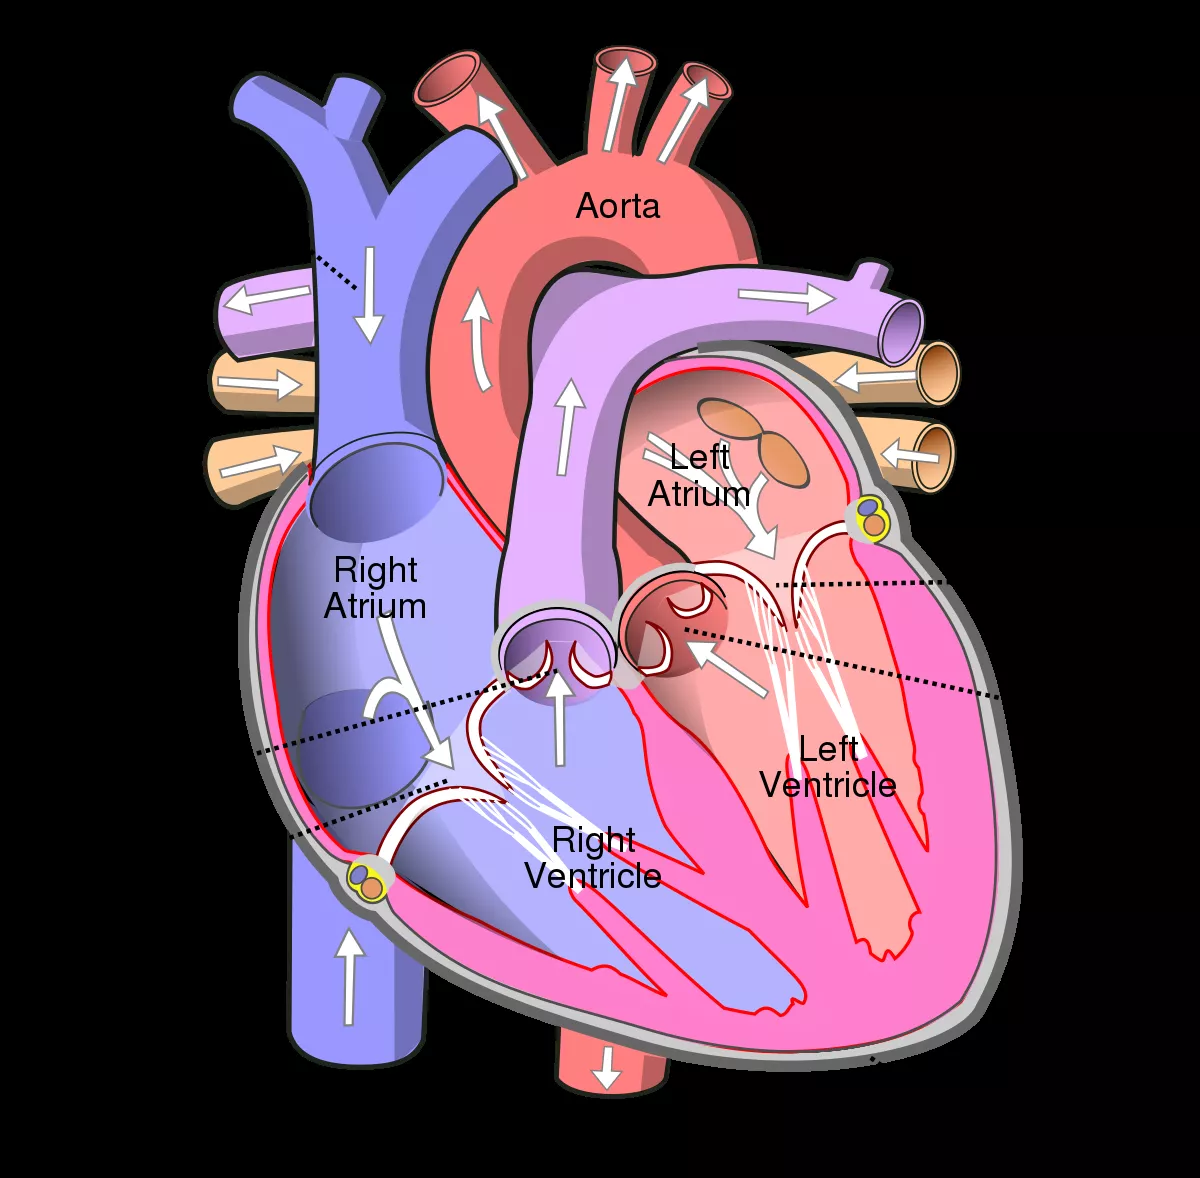

What Is The Diagram Of Human Heart 3 diagram 4 chart chart table graph diagram chart

What Is The Diagram Of Human Heart

What Is The Diagram Of Human Heart

What Is The Diagram Of Human Heart

What Is The Diagram Of Human Heart

Human Heart Labeled Heart Diagram Human Heart Diagram Heart Blood Flow

Human Heart Biology